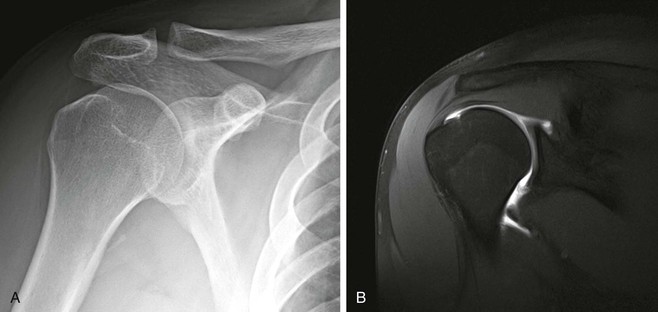

Optimal conventional radiographic views have been described for identifying these variations of the osseous outlet.71-74 The AP radiograph at a 30-degree caudal angle (Fig. 44-8) is helpful in visualizing the anterior aspect of the acromion and in detecting inferiorly directed enthesophytes.72 A modified transcapular lateral view obtained with 10 to 15 degrees of caudal angulation (the supraspinatus outlet view) helps further identify the anteroinferior aspect of the acromion.75 A high-riding humeral head with remodeling of the undersurface of the acromion and sclerosis of the greater tuberosity are conventional radiographic findings (Fig. 44-9) that are pathognomonic of a chronic rotator cuff tear. Although conventional arthrography, ultrasonography, and CT offer improved visualization of the rotator cuff relative to conventional radiography, they add little in the direct evaluation of the osseous outlet.

Conventional radiography is often complementary to more sophisticated imaging techniques in the evaluation of glenohumeral instability. The imaging protocol for conventional radiography varies, depending on personal preference, but it should include the basic views, which will enhance the detection of osseous abnormalities. For patients with a history of antecedent trauma, views should be selected that optimize visualization of the Hill-Sachs deformity, anterior trough defect, and Bankart lesion.136 The Garth view,137 the AP view with the shoulder in internal rotation, the axillary view, and the Stryker notch view improve detection of the posterior Hill-Sachs deformity and of the anterior trough defect (see Fig. 44-35). The anterior and posterior glenoid rim is best imaged on the axillary view or one of its many variations. An osseous Bankart lesion involving the anteroinferior glenoid rim is best visualized on the Garth view or the West Point view.3 The patient's condition should also be taken into consideration in selecting radiographic views because the standard axillary view may be difficult to obtain in the setting of acute trauma. In these situations, one of the many axillary variants may be easier to obtain. In the setting of recurrent subluxation with no antecedent trauma, it is recommended that two tangential views be obtained to identify subtle subluxation of the humeral head. A true anteroposterior glenohumeral (Grashey) view will aid in the detection of inferior subluxation, and one of the axillary view variants will demonstrate anterior or posterior subluxation.

The radiographic findings associated with glenohumeral instability include the Hill-Sachs and Bankart osseous abnormalities, which occur when the posterior aspect of the humeral head has an impact on the anteroinferior glenoid rim at the time of anterior dislocation. The Hill-Sachs lesion is seen as flattening or a wedge-shaped defect involving the posterosuperior aspect of the humeral head; the bony Bankart lesion is seen as a small fracture or area of cortical irregularity involving the anteroinferior glenoid rim. Although these radiographic findings lack sensitivity, they are specific for previous anterior dislocation and indicate that injury has occurred to the labroligamentous complex, which may predispose the patient to recurrent glenohumeral instability. At the time of posterior dislocation, the anterior aspect of the humeral head has an impact on the posterior glenoid rim, creating an anterior trough defect in the anterior aspect of the humeral head and a “reverse Bankart” lesion involving the posterior glenoid rim. Subluxation can be a subtle radiographic finding that may indicate glenohumeral instability, and it is best detected on tangential views of the glenohumeral joint. The center of the humeral head should be centered within the glenoid fossa, and any asymmetry may indicate subluxation or persistent dislocation (Box 44-5).